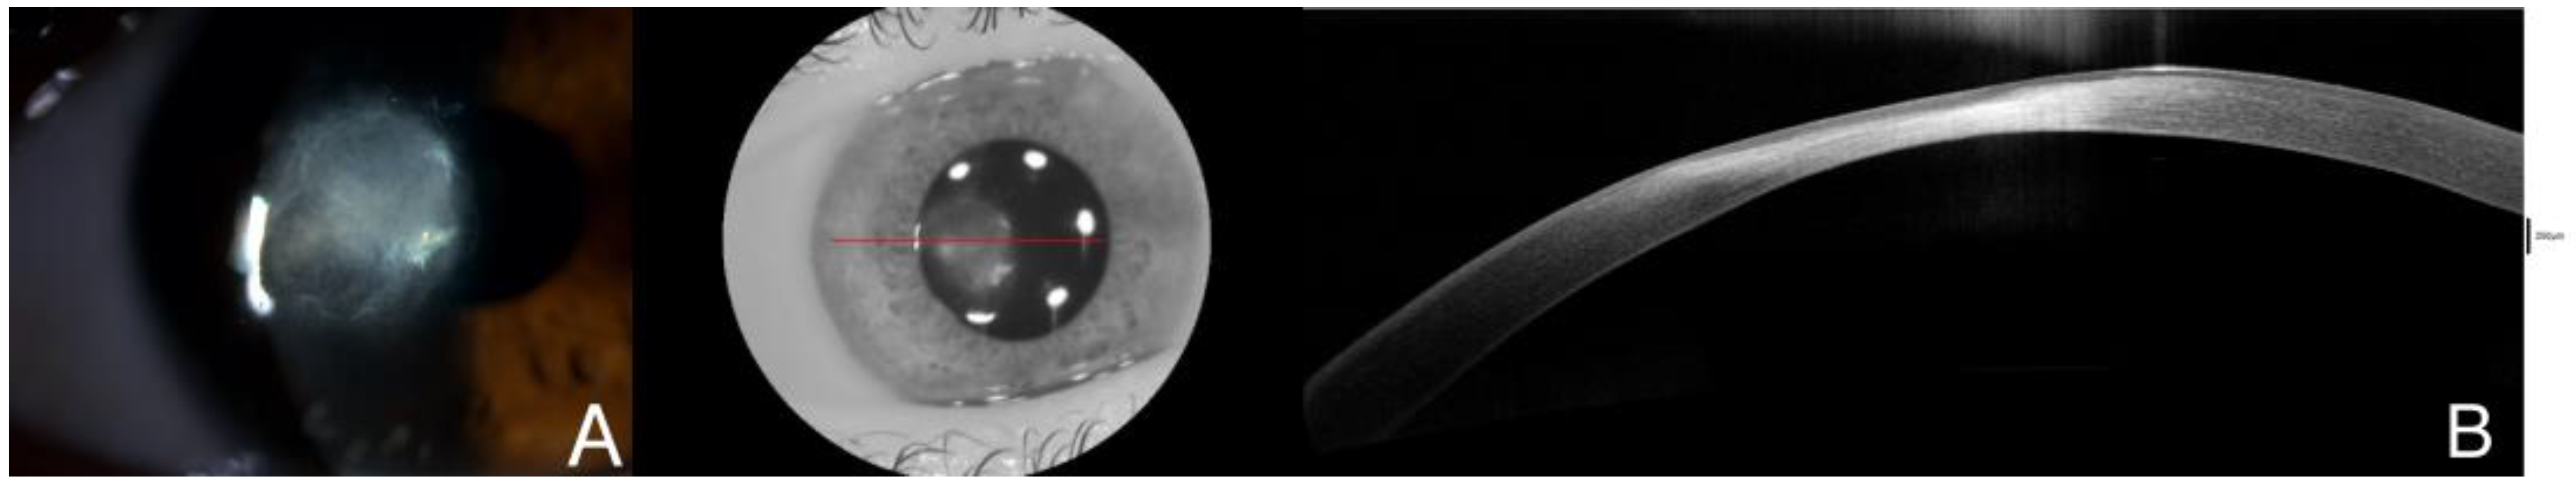

Figure 3.

Corneal debridement and biopsy were performed, along with intrastromal infiltration with amphotericine and cefuroxime. A total of 24 h after the procedure, the infiltrate appeared smaller with a large epithelial defect in both clinical examination (A) and AS-OCT (B), which also displayed intrastromal cysts and hyperreflectivity in both stroma and epithelium, as well as edema and cystic spaces, along with tissue defects due to the surgical procedure. The red line is correspondene of the en face picture with the selected section on the AS-OCT.